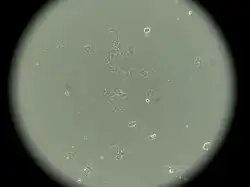

MCF-7 (Michigan Cancer Foundation-7) — эпителиоподобная клеточная линия, полученная из инвазивной аденокарциномы протоков молочной железы человека[1][2].

Линия была получена в 1973 году Гербертом Соулом и его сотрудниками в Институте рака Барбары Энн Карманос. До получения линии MCF-7 исследователи не могли получать линии клеток молочной железы, способной жить дольше нескольких месяцев. Сегодня эта линия является одной из наиболее распространенных линий клеток для исследований in vitro цитотоксичности противоопухолевых фармпрепаратов, молекулярной биологии рака[3], а также цитосовместимости различных биосовместимых материалов[2].